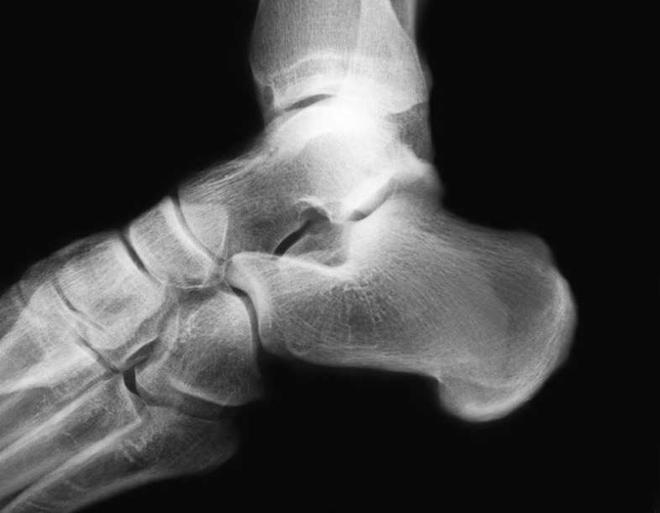

Fractura del calcáneo o talón

Es la rotura del hueso del talón o calcáneo, situado en la base de la planta del pie lo que impide el apoyo del mismo en el suelo.

Suele estar provocada por una caída brusca sobre el talón o bien por un fuerte golpe en la zona.